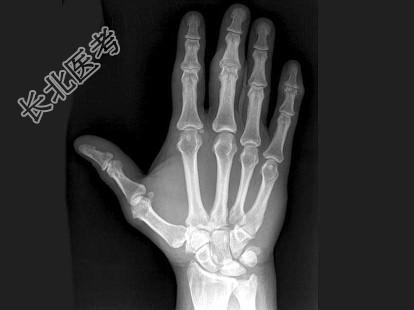

- 单项选择题男,24岁, 双手疼痛,结合图像, 最可能的诊断是 ( )

A、肢端肥大症

B、骨质疏松症

C、类风湿关节炎

D、痛风

E、维生素D缺乏症